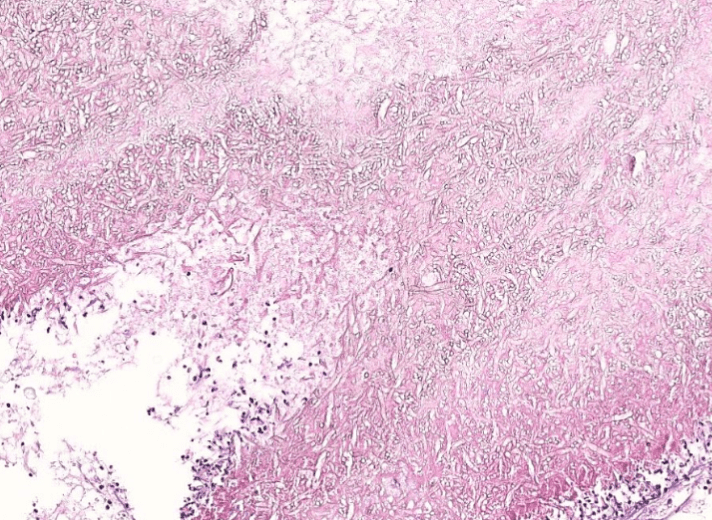

lung adenocarcinoma